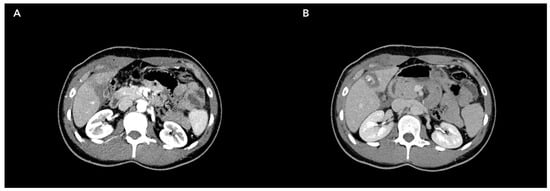

- Wang, H.; Bao, Q.; Cao, D.; Dong, S.; Wu, L. Characteristics of Computed Tomography Images for Patients with Acute Liver Injury Caused by Sepsis under Deep Learning Algorithm. Contrast Media Mol. Imaging 2022, 2022, 9322196. [Google Scholar] [CrossRef]